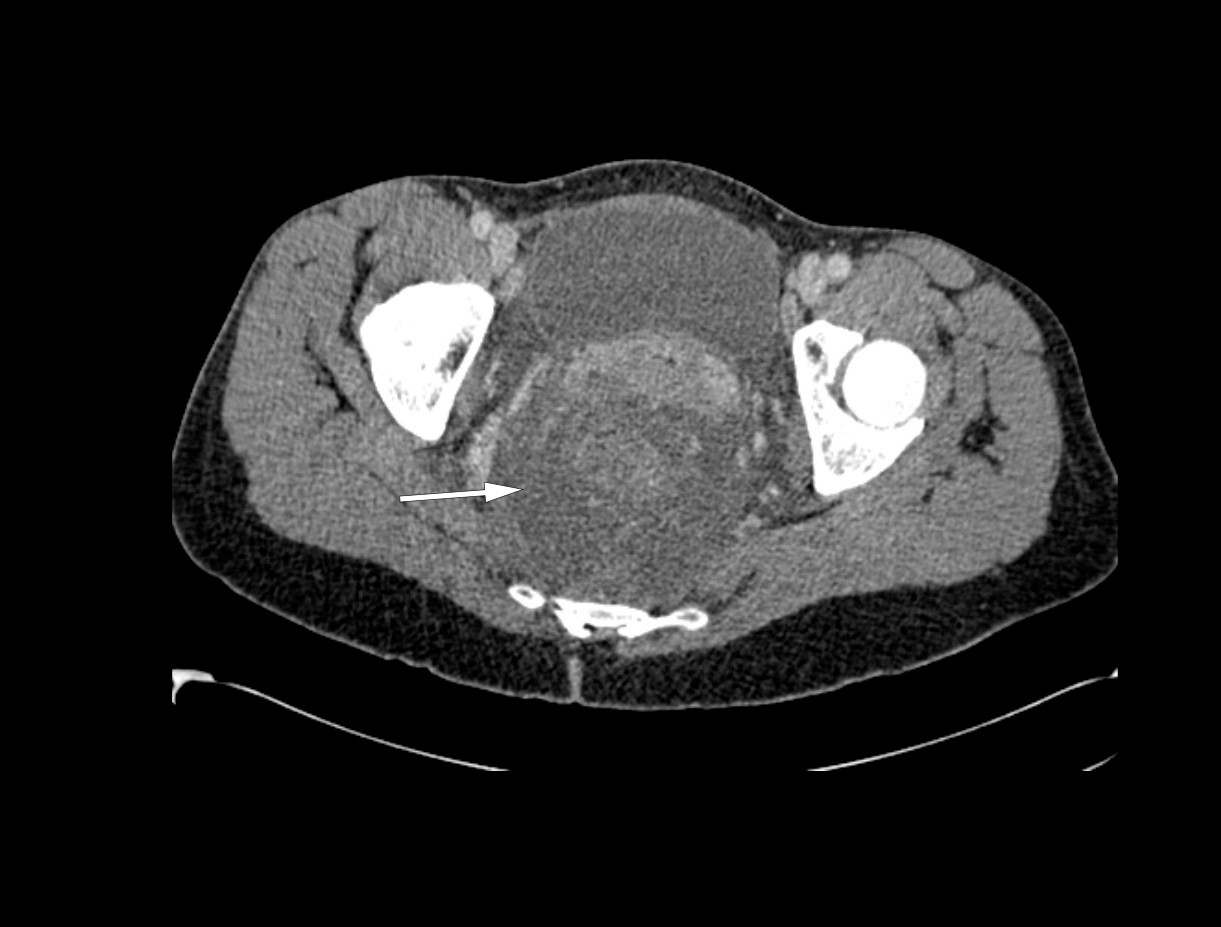

Knapt to timer etter innleggelsen ble det utført CT av thorax, abdomen og bekken med intravenøs kontrastvæske. Det ble ikke gitt peroral eller rektal kontrast. I thorax ble det ikke påvist noen aktuell patologi. CT av bekken viste en uttalt ødematøst fortykket rektumvegg på opptil 2 cm, fra sigmoidovergangen i promontorienivå til anus. Det var ikke patologisk gass i bløtvevet, men et mesorektalt ødem som strakte seg sammenhengende retroperitonealt til nyrevenenivå. Det var moderat mengde fri væske i peritonealhulen i nedre abdomen og bekken. I peritoneum var det ingen fri luft. Parenkymatøse organer og genitalia interna var uten funn. Sigmoideoskopi viste proktittforandringer med ødematøs slimhinne og rubor i distale 10 cm av rektum. Det var ikke tegn til tarmperforasjon eller tarmiskemi.

På grunn av klinisk forverring uten respons på igangsatt behandling og mistanke om abdominalt infeksjonsfokus, ble det gjort laparotomi. Man fant rikelig ascites i bukhulen og retroperitonealt ødem fra øvre nyrepol på begge sider som strakk seg ned i bekkenet og mesorektum. Det var ingen tegn til intraabdominale abscesser eller tarmperforasjon. Funnene var ikke forenlig med nekrotiserende fasciitt, idet man fant viabelt vev uten tegn til gassdanning, krepitasjoner eller henfall. Det ble gjort reseksjon av colon sigmoideum og rektum ned til analkanalen med anleggelse av endekolostomi. Retroperitoneum ble åpnet og drenert for væske. Det ble tatt bakteriologisk undersøkelse av ascites og retroperitonealvæsken. Buken ble midlertidig lukket med vakuumbandasje, slik at vi senere kunne gjøre en ny vurdering. Etter å ha konferert med infeksjonsmedisiner ble antibiotikabehandling endret til meropenem 1 g × 3 intravenøst for å oppnå bedre penetrans til bløtvev.

Hos vår pasient viste CT av buken omfattende ødem perirektalt og retroperitonealt. Sigmoideoskopi viste proktitt. På bakgrunn av dette mistenkte man primært en gramnegativ infeksjon og opererte pasienten med rektumreseksjon med distal avsetting helt ned på analkanalen. Direkte mikroskopi av ødemvæsken burde vært gjort under primærinngrepet, da påvisning av streptokokker trolig ville medført at man gjorde analamputasjon ved primæroperasjonen for å sanere inngangsporten for infeksjonen. Sigmoideum var ødematøs og betent og måtte recesseres. Direkte mikroskopi under primærinngrepet ville ikke påvirket denne avgjørelsen eller omfanget av reseksjonen.